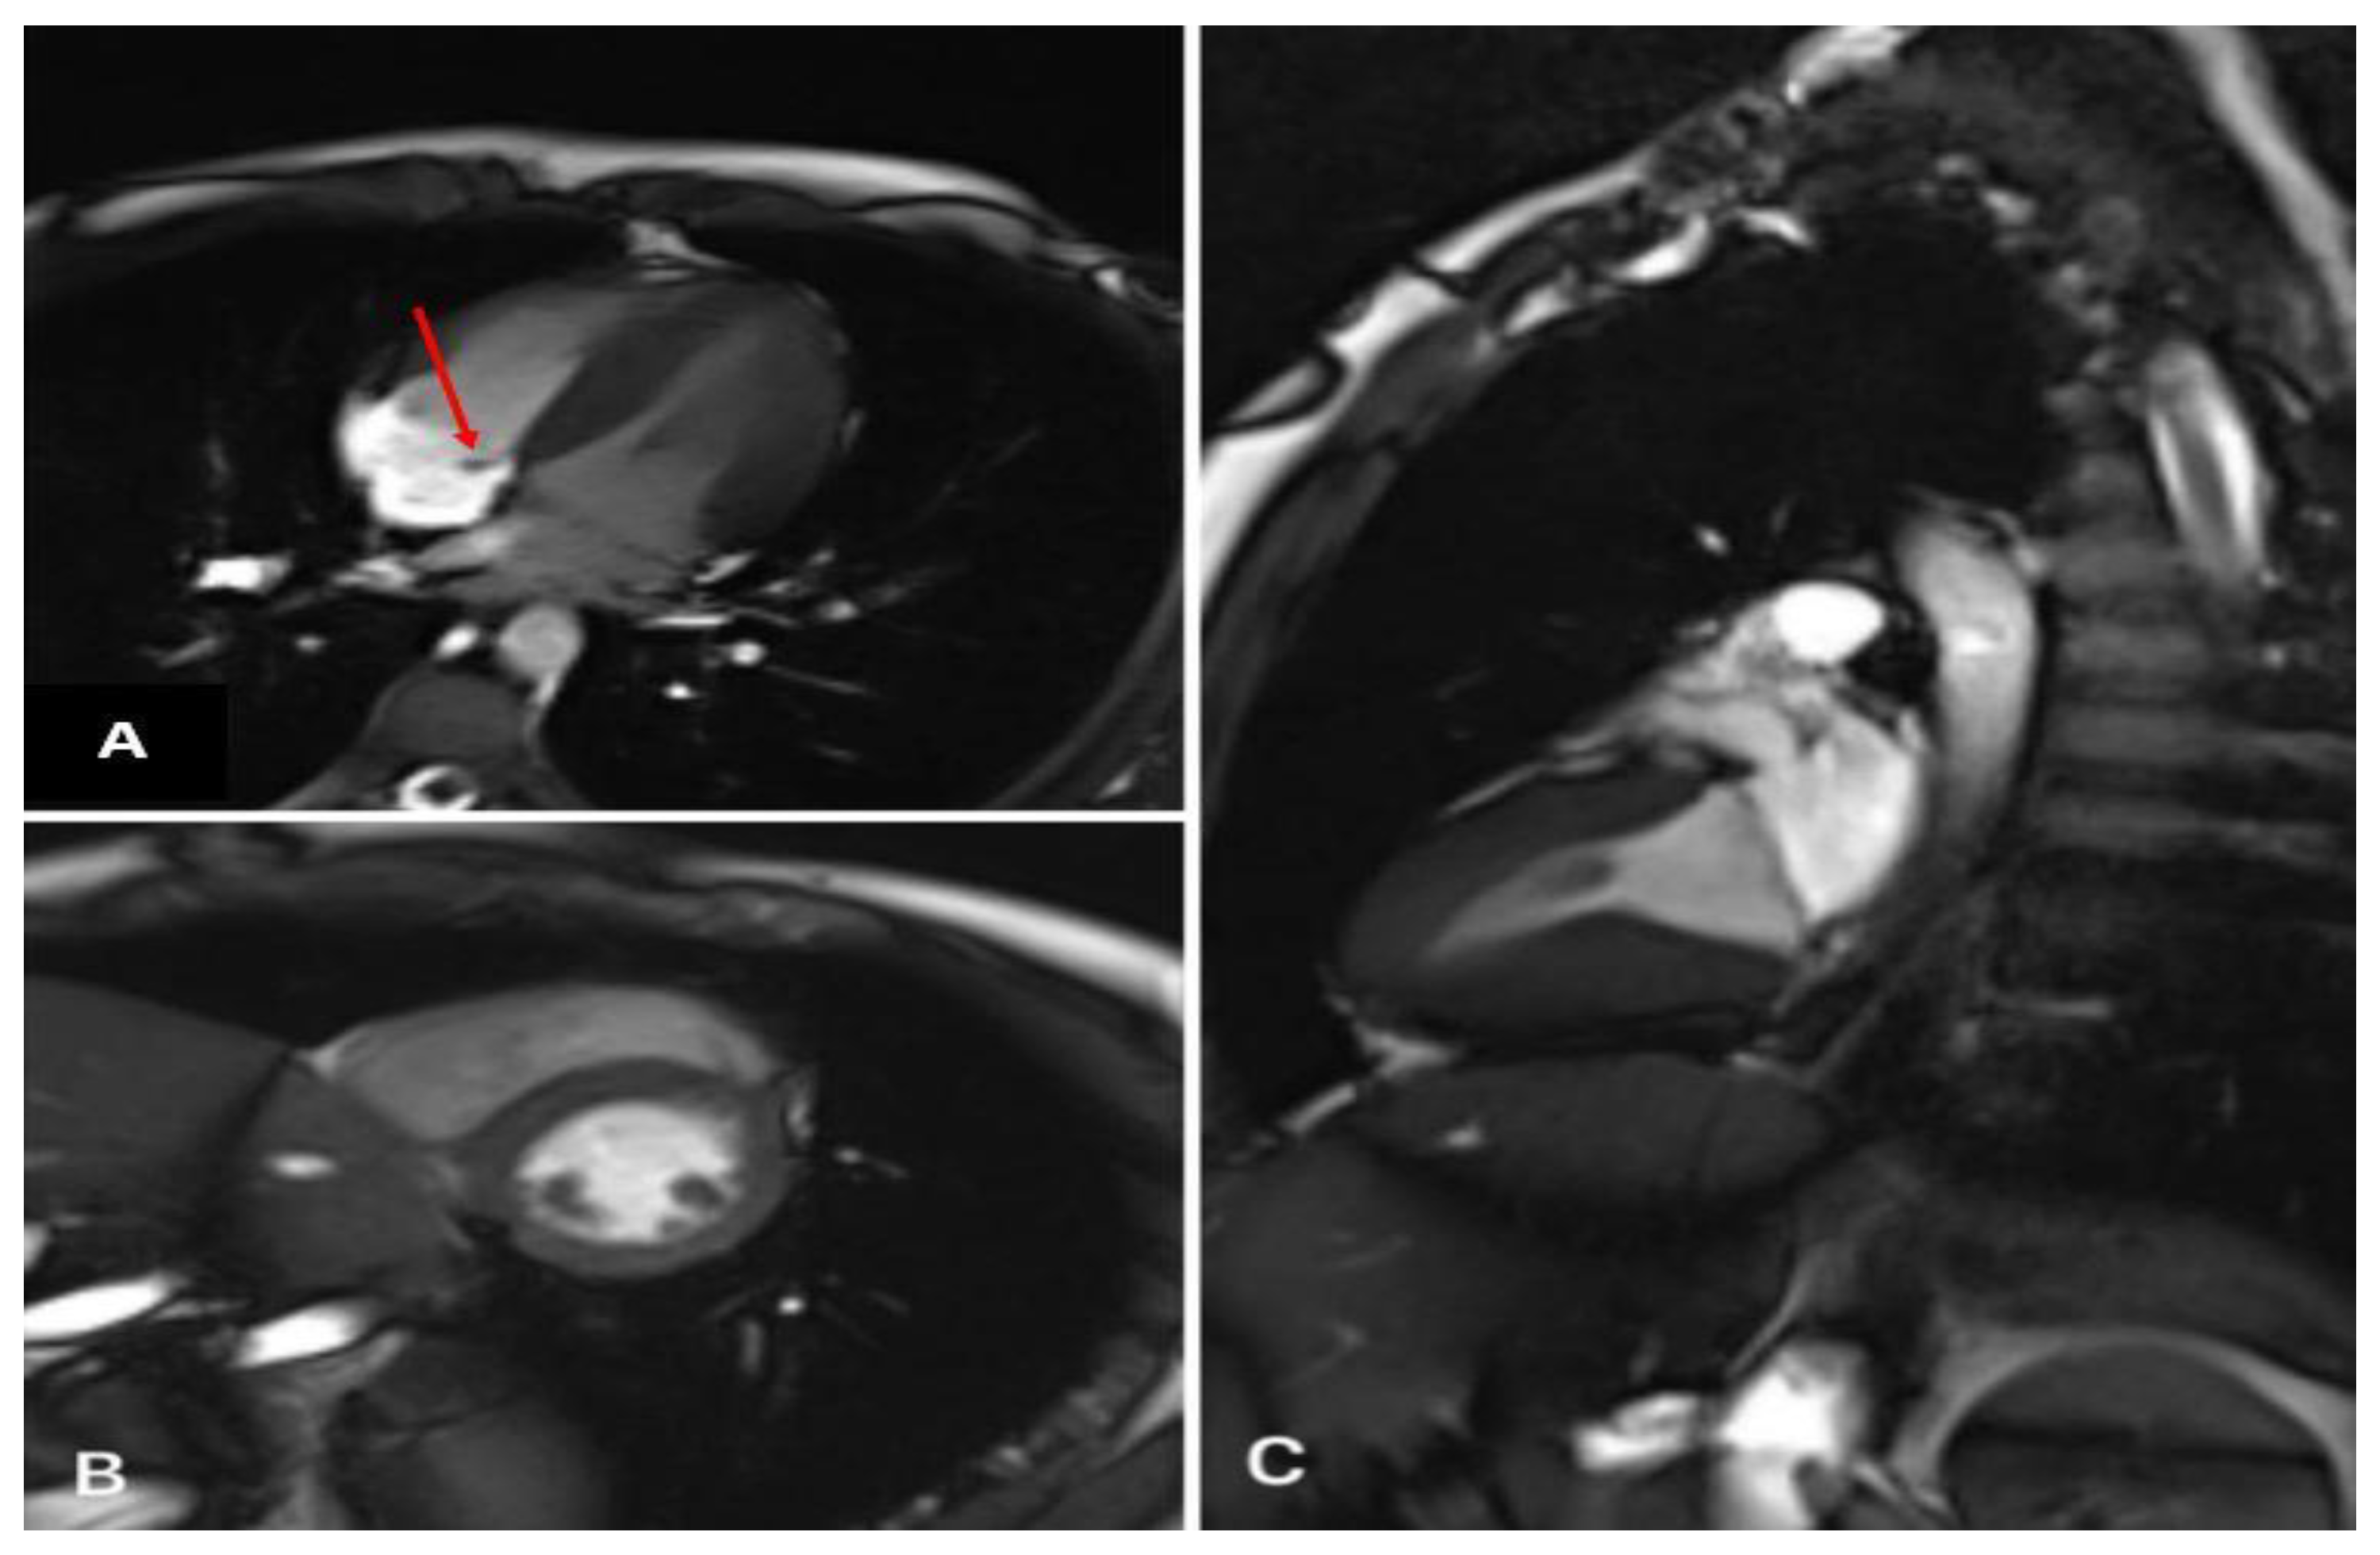

A formation with clear contours was determined. There were no signs of myocardial edema. On delayed post-contrast images, there was no distinct pathological accumulation of the contrast agent in the myocardium (Figure 2).

Figure 2.

Heart MRI with contrast. (A) Four-chamber plane (formation of a septal valve—red arrow). (B) Two-chamber plane along the short axis (normal). (C) Two-chamber plane along the long axis (norm).

Signs of the signal enhancement on Tirm due to edema of the IVS myocardium were revealed on the heart MRI data with contrast, which indicated inflammatory changes in the myocardium three weeks later (Figure 5 and Figure 6).

Figure 5.

Heart MRI with contrast. Arrows indicate myocardial edema in the region of the interventricular septum.